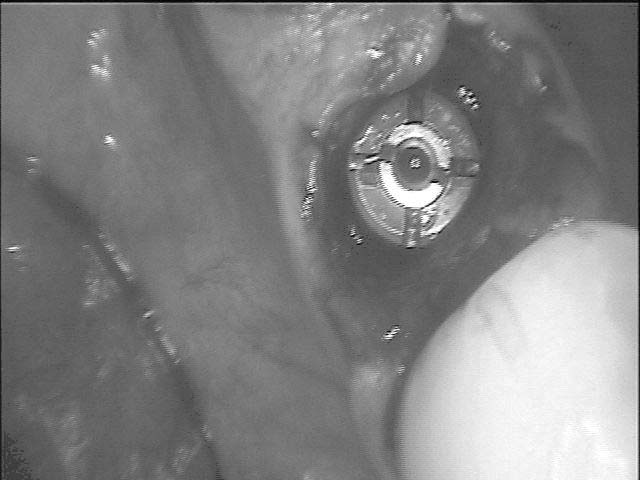

斷裂蛀蝕牙根

拔牙+植牙